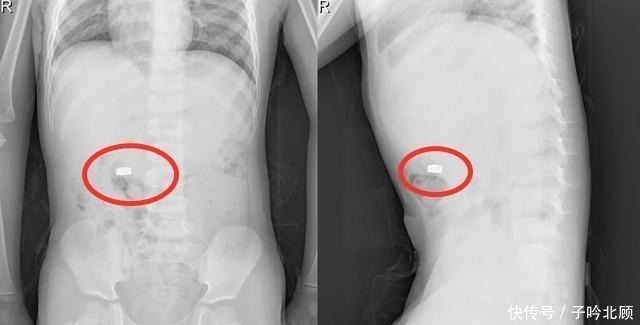

原来5岁的儿子正在向李女士炫耀自己的成果,孩子居然把纽扣电池吃到了嘴里,而且还做出了一副洋洋得意的表情!李女士瞬间感觉到大事不好,于是赶紧带着孩子去医院检查了一下。也多亏李女士带孩子来得及时,不然的话纽扣电池就会把孩子身体给腐蚀的。所幸孩子最终并无大碍,但父母也应当提高安全意识,家里的这些东西一定要提醒孩子远离它们1、家用电器